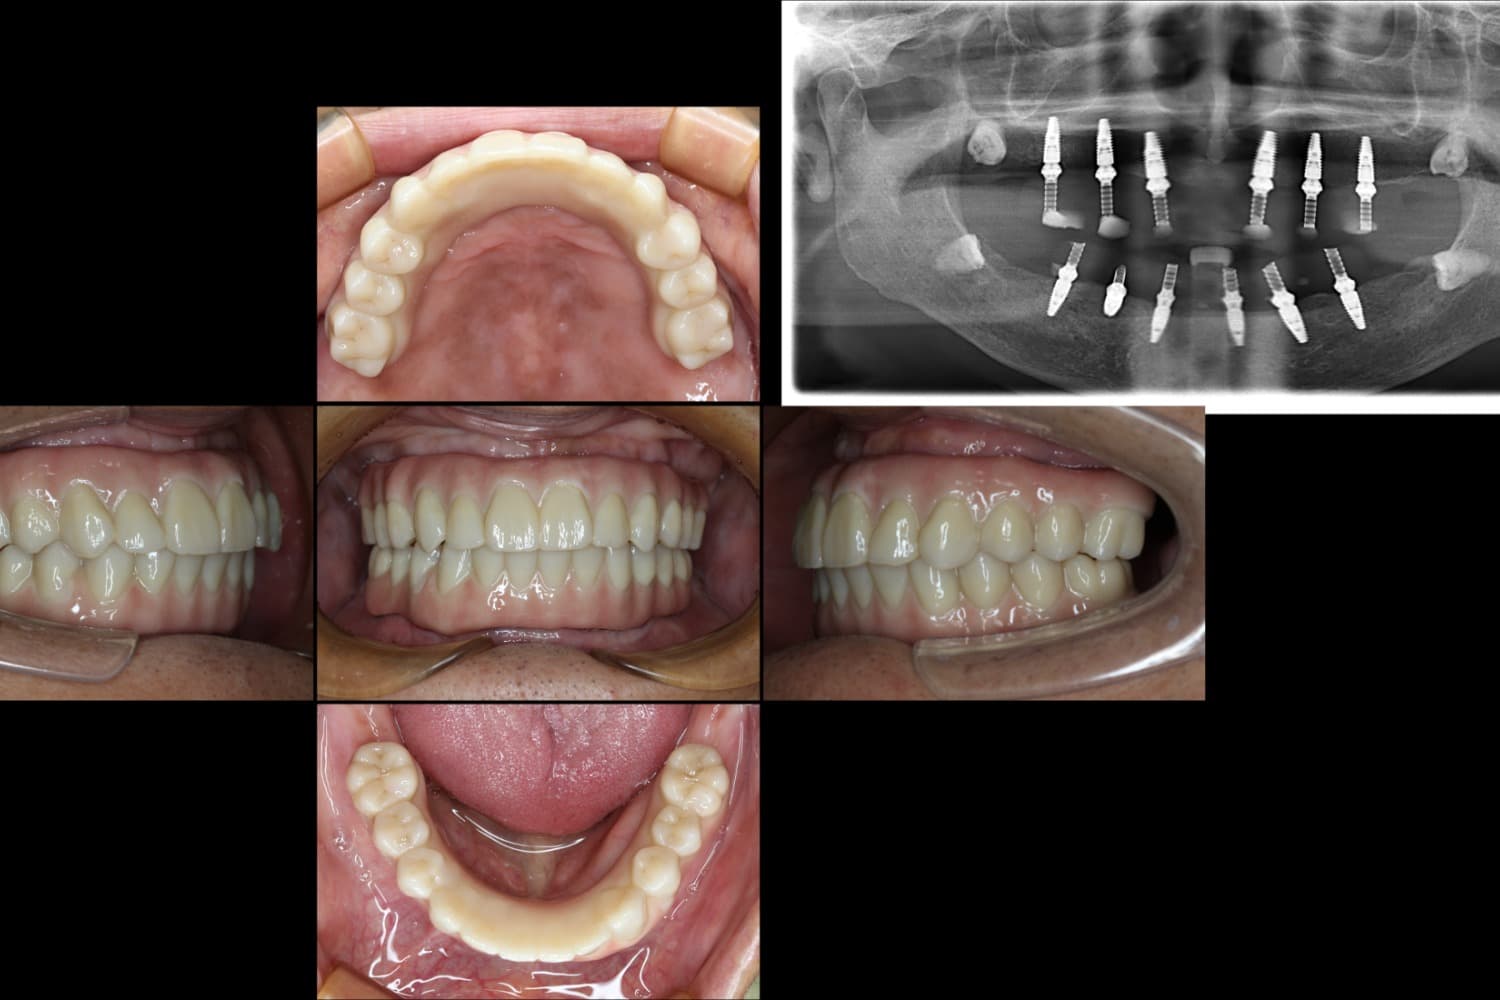

All-on-6による治療

After

All-on-6という全部の歯をインプラントで補う治療 保存できる歯がない状態になっており、食事がまともにできないとのことでした。 インプラントを移植すると同時に被せ物も一緒に装着する方法で機能回復をおこないました。

年齢

70代

性別

男性

主訴

入れ歯が合わず、食事ができない

治療期間

5ヵ月

治療回数

10回

費用

CT 16,500円(税込) 静脈内鎮静法 66,000円(税込) ALL-ON-6 2,750,000円(税込)×2

副作用・リスク

歯周病に感染・発症し重度に進行するとインプラントが抜けてしまうことがあります。また、手術後は数日間腫れが出る場合があります。